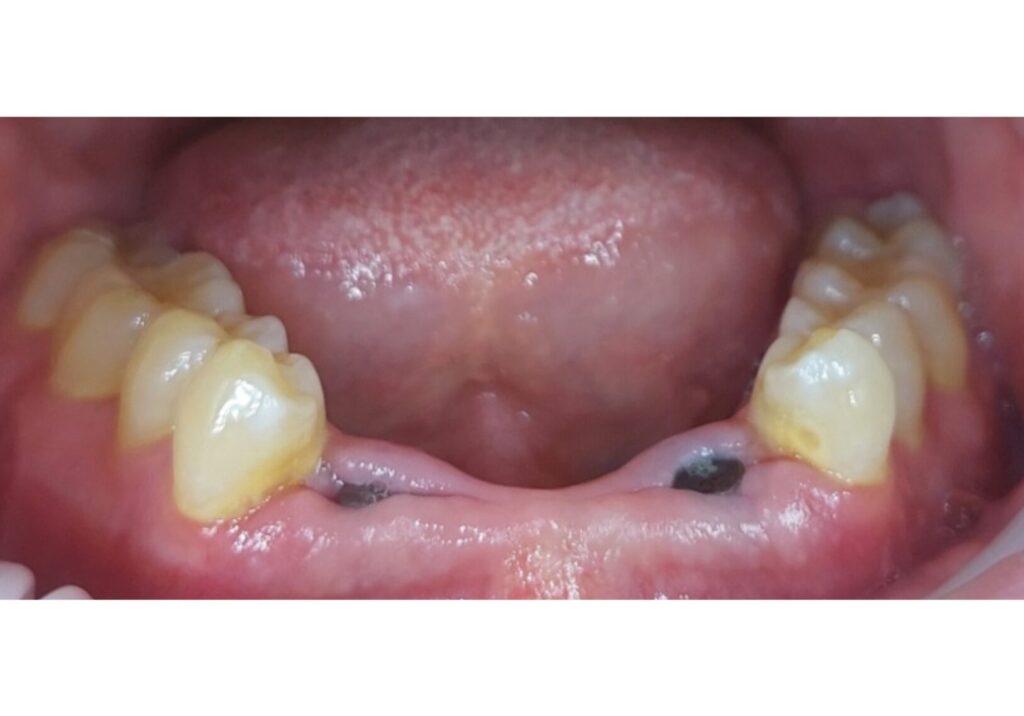

Prieš

Po

Gyd. Lukas Mingaila

Apatinių priekinių dantų atkūrimas implantais po traumos. Implantavo gyd. Osvaldas Norinkevičius.

Gegužės g. 1, Klaipėda

Prisidėję gydytojai: Osvaldas Norinkevičius